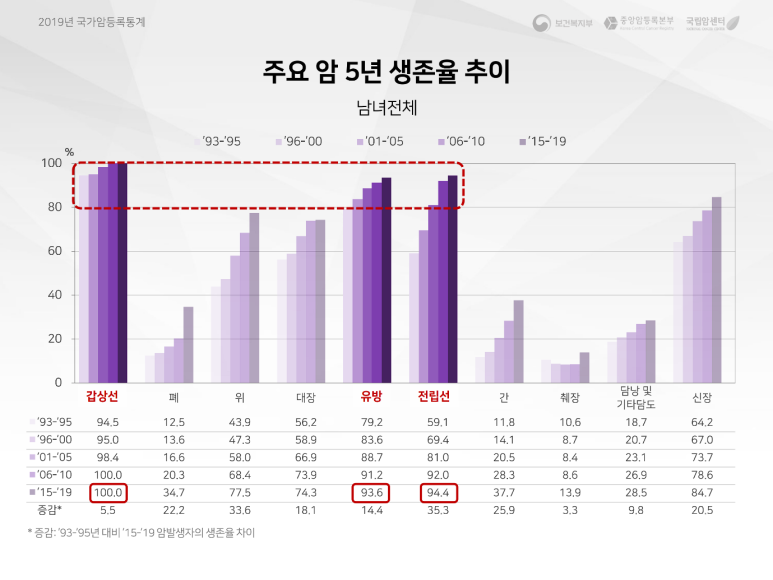

이러한 높은 발생률에도 불구하고 다행히 갑상선암은 예후가 좋은 것으로 나타나고 있습니다.

겉으로 막대기가 높을수록 좋은 예후를 기대할 수 있다고 생각하세요. 특히 다른 암종에 비해 5년 생존율이 가장 높은 것으로 확인되고 있습니다.위의 통계자료를 요약하면 갑상선암은 우리나라에서 발생률이 가장 높은 암종(2019년 기준)으로 주로 젊은 사람에게 유발되지만 예후가 매우 좋은 것으로 나타나고 있습니다.